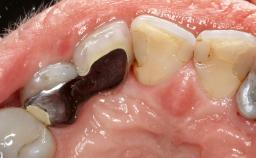

Late Presentation of Peri-Implant Mucositis Requiring Soft-Tissue Augmentation and Esthetic Crown Lengthening at Implant Site 11